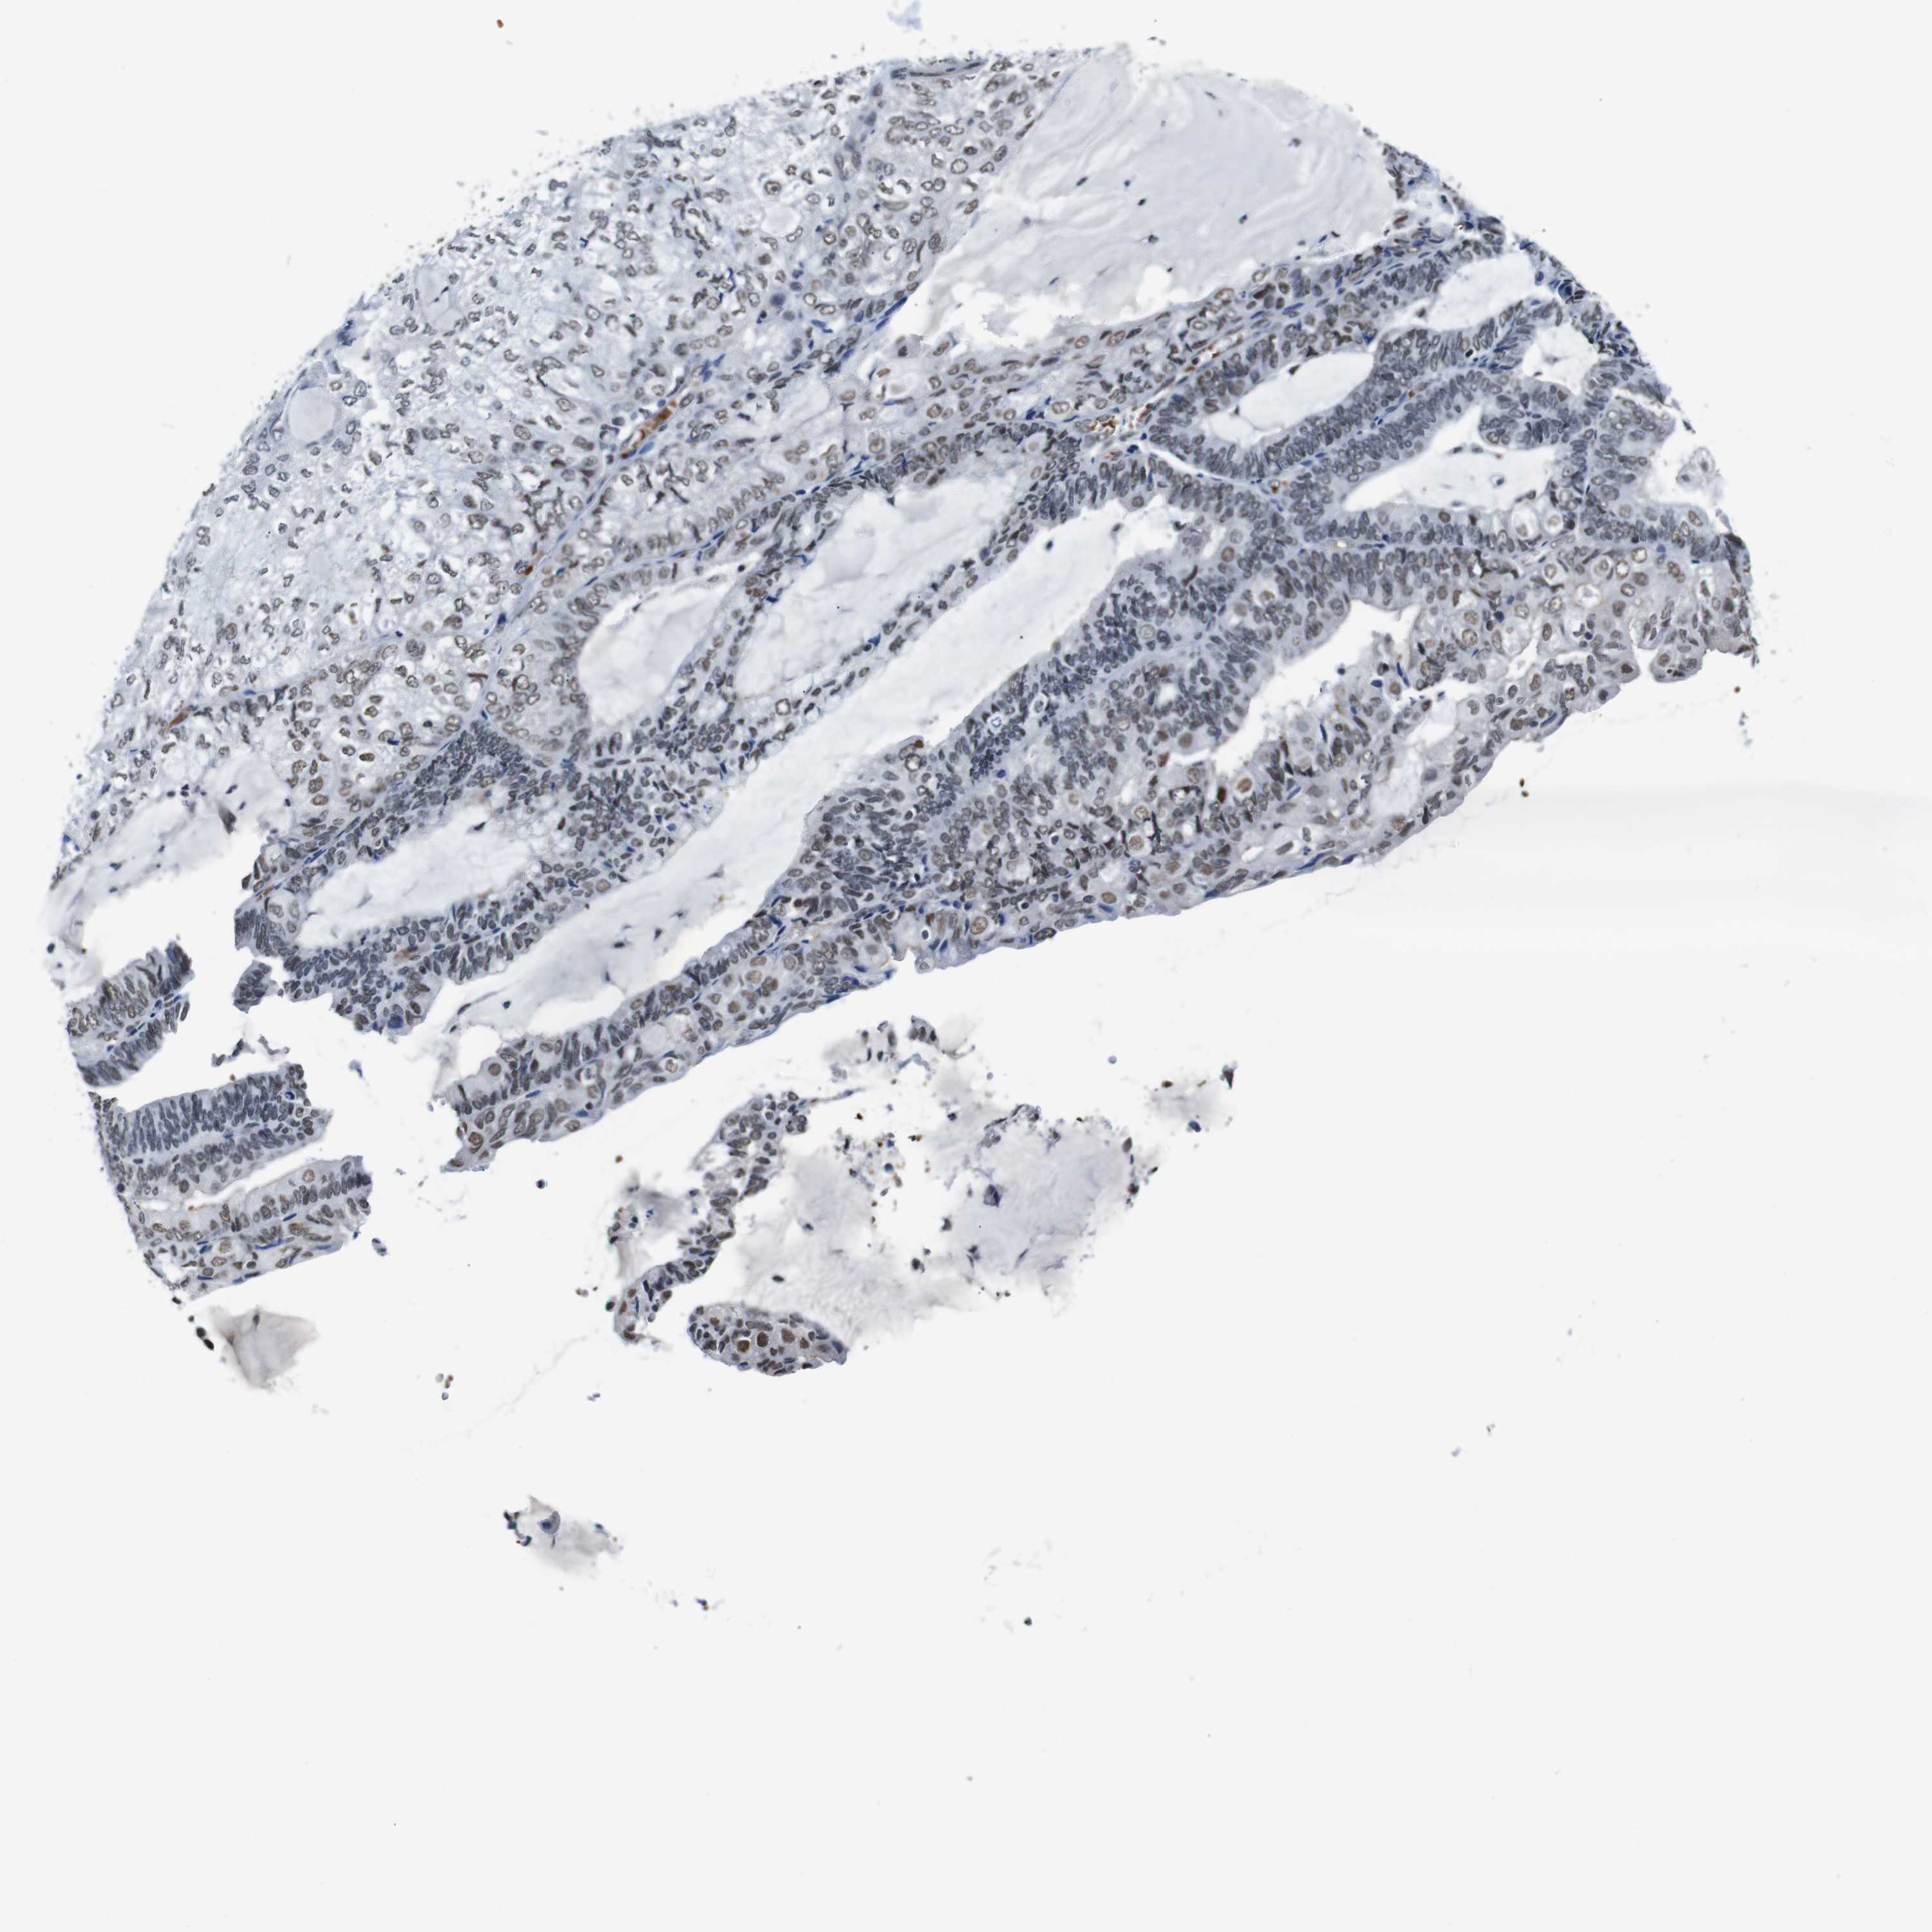

ENDOMETRIAL CANCER - Protein expressioni

A mouse-over function shows sample information and annotation data. Click on an image to view it in a full screen mode. Samples can be filtered based on level of antibody staining by selecting one or several of the following categories: high, medium, low and not detected. The assay and annotation is described here.

Note that samples used for immunohistochemistry by the Human Protein Atlas do not correspond to samples in the TCGA dataset.

Antibody stainingi

Antibody staining in the annotated cell types in the current human tissue is reported as not detected, low, medium, or high, based on conventional immunohistochemistry profiling in selected tissues. This score is based on the combination of the staining intensity and fraction of stained cells.

Each image is clickable and will lead to virtual microscopy that enables deeper exploration of all samples and also displays staining intensity scores, fraction scores and subcellular localization as well as patient and tissue information for each sample.

Antibody HPA012545

Staining

High

Medium

Low

Not detected

Intensity

Strong

Moderate

Weak

Negative

Quantity

>75%

75%-25%

<25%

None

Location

Nuclear

Cytoplasmic/membranous

Cytoplasmic/membranous,nuclear

Adenocarcinoma, NOS

Neoplasm, malignant, NOS